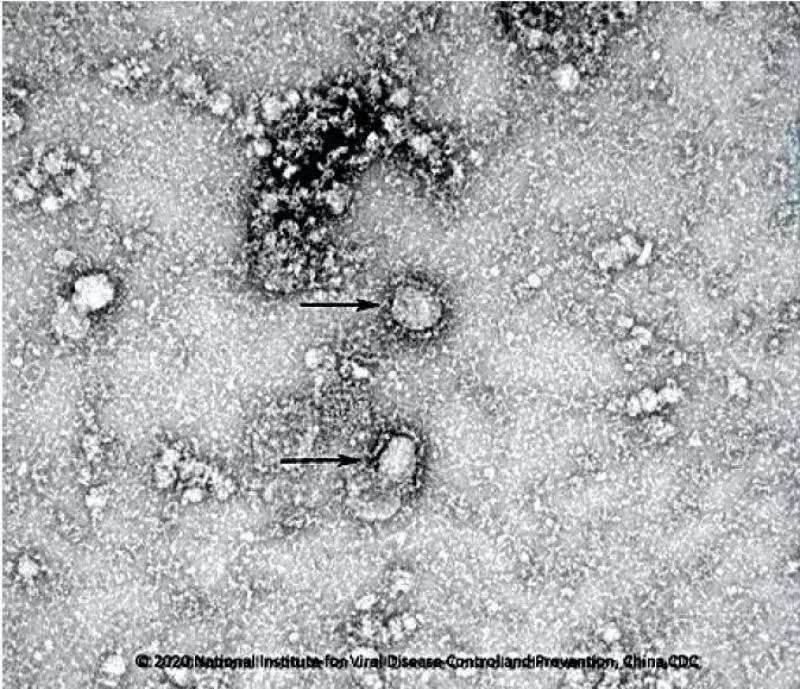

Theo hãng tin RT, chính quyền Trung Quốc vừa công bố những hình ảnh cận cảnh đầu tiên về virus corona. Loạt hình ảnh này do Viện Vi sinh của Học viện Khoa học Trung Quốc công bố ngày 24/1 (giờ địa phương).

Cận cảnh virus corona. Ảnh: Viện Vi sinh, Viện Hàn lâm Khoa học Trung Quốc.